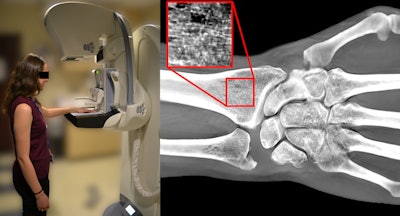

"Digital wrist tomosynthesis is feasible in a mammography setting, and informative on bone mass, cortical thickness, and microstructural qualities that are known to deteriorate in osteoporosis," wrote the authors, led by Yener Yeni, PhD, a biomechanics researcher at the Henry Ford Health System Bone and Joint Center in Detroit. "To our knowledge, this study represents the first application of DBT for imaging bone."

After confirming ex-vivo feasibility, the team recruited five patients, ranging in age from 19 to 75, to undergo wrist tomosynthesis scans. To acquire the digital wrist tomosynthesis (DWT) images, the patients aligned their nondominant, left hand on a generic hand template the researchers taped to a DBT machine.

The team acquired DWT images three times, repositioning the patients' arms to acquire views from different angles. The researchers then used computer calculations to quantify bone mineral density metrics from the DWT images.